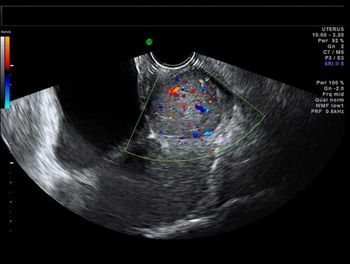

What is your diagnosis in this middle-aged woman with abnormal vaginal bleeding?